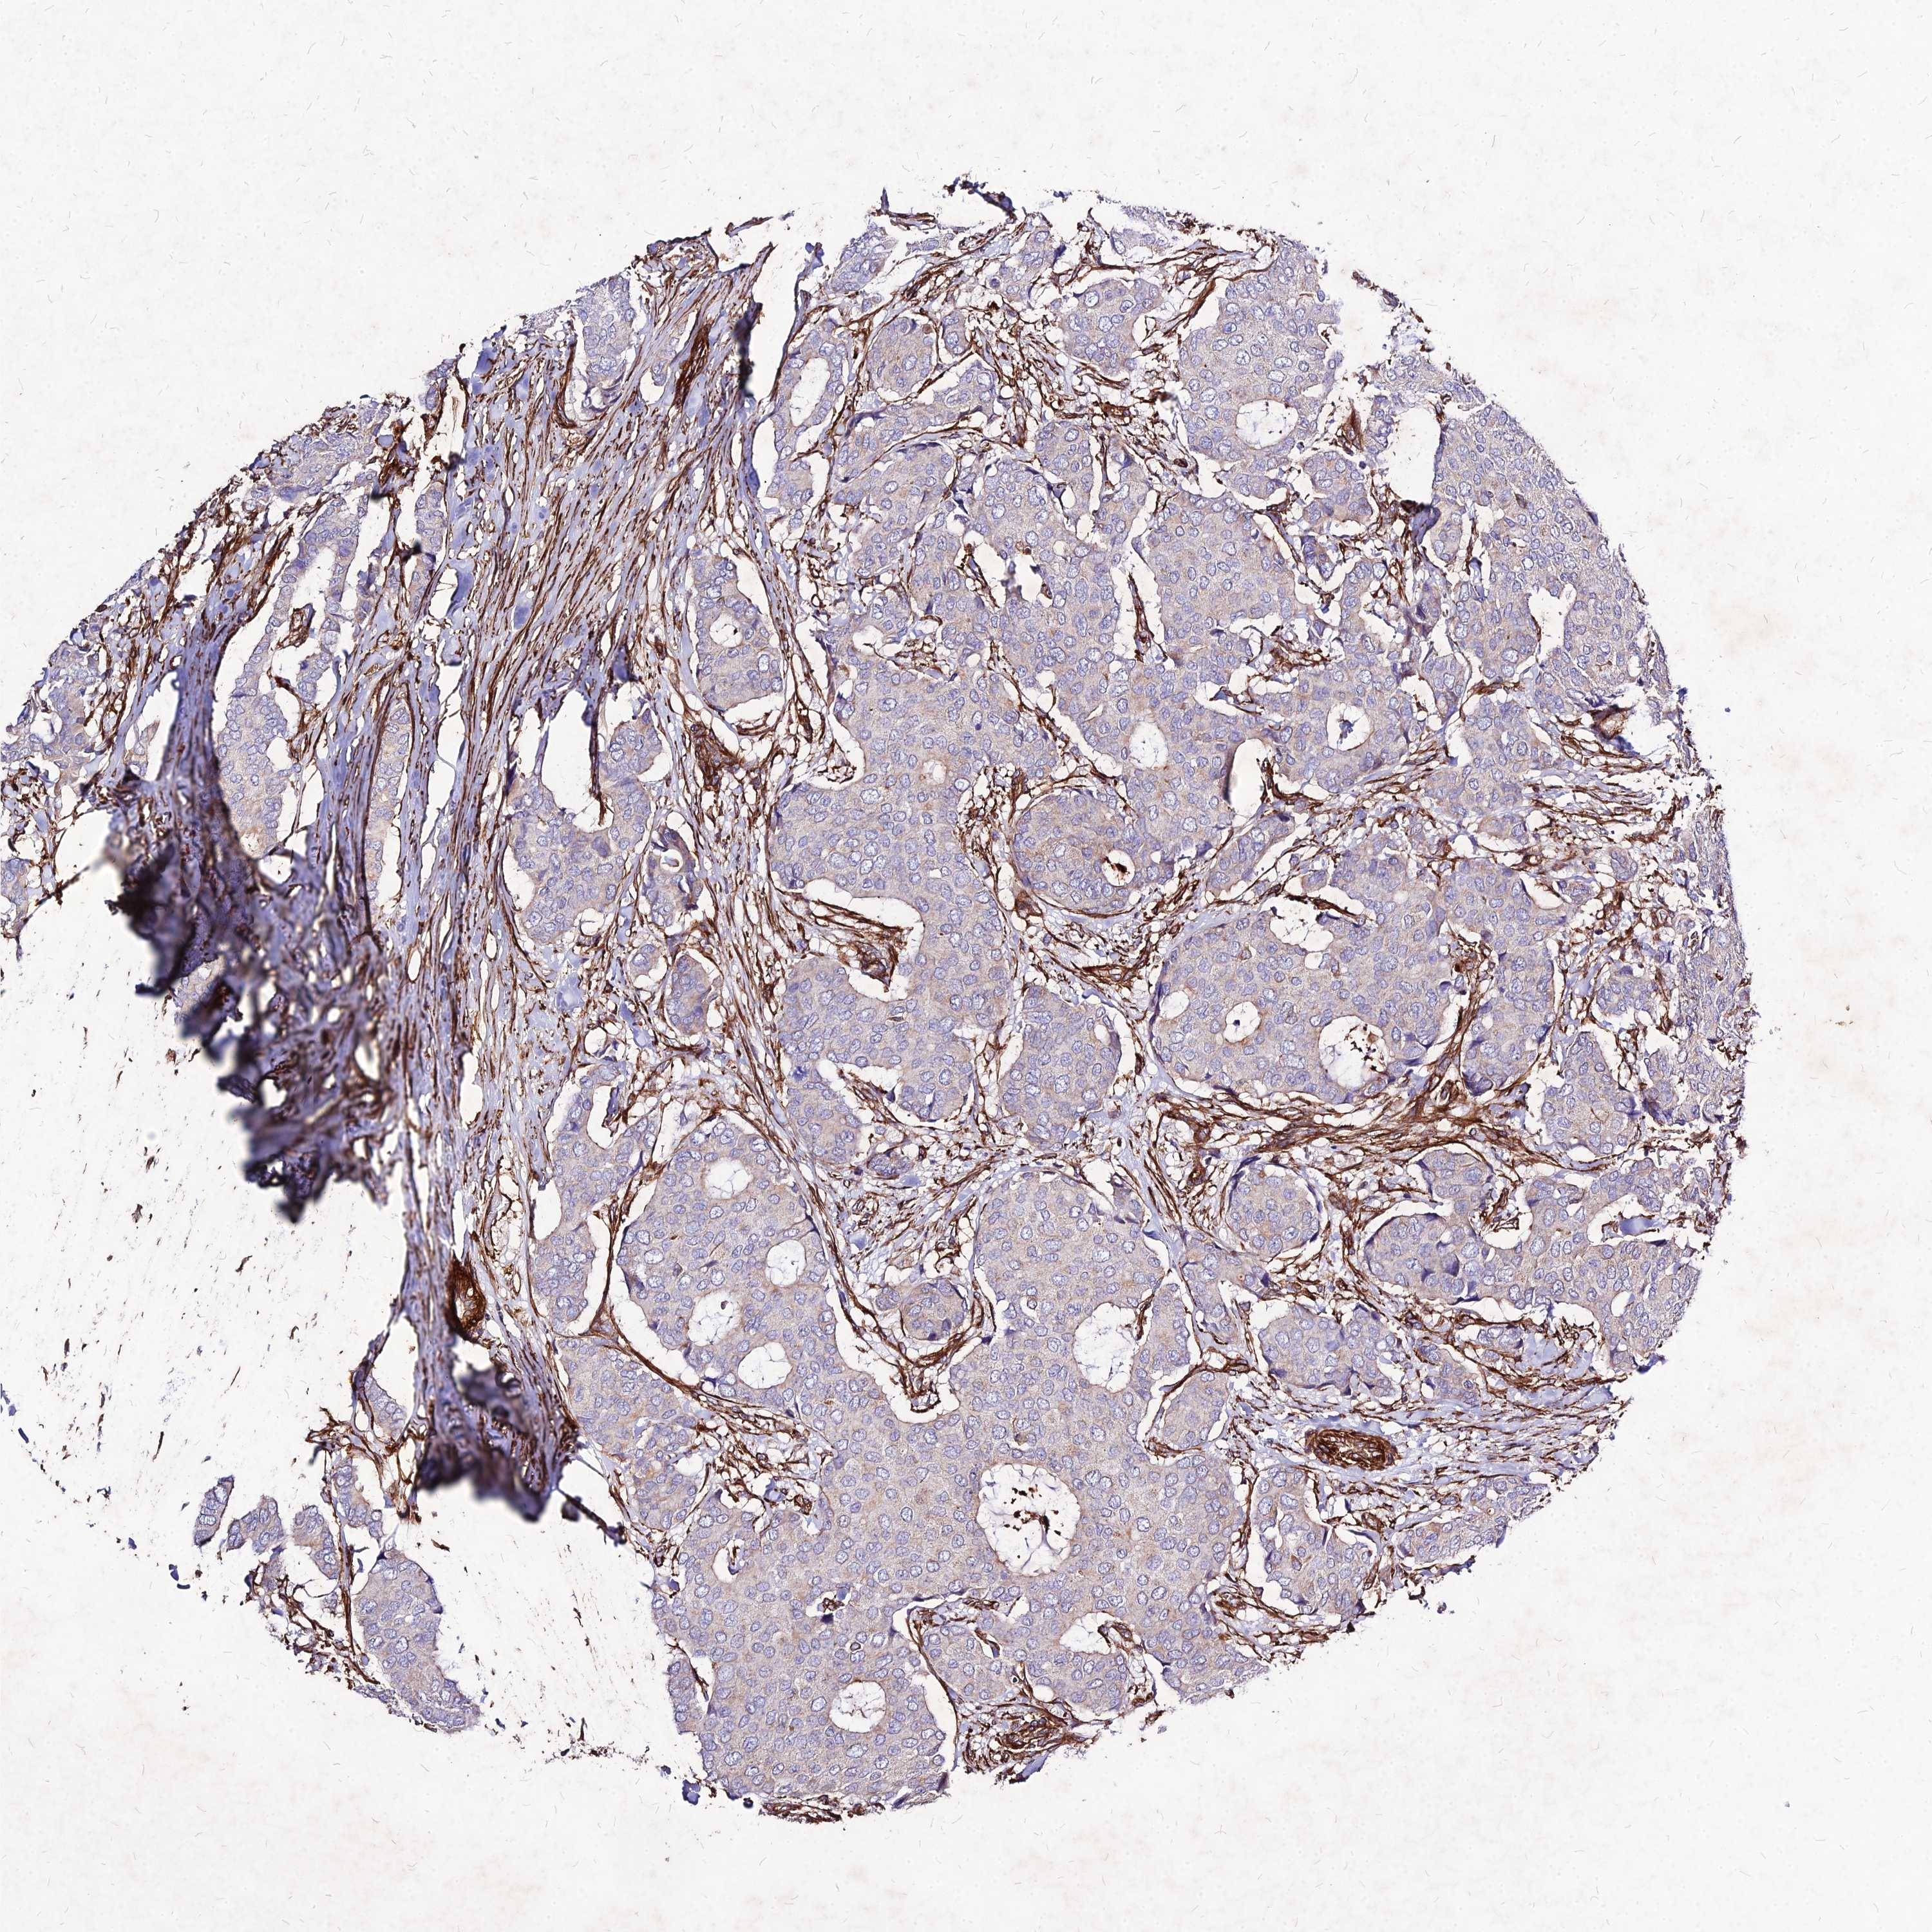

CANCER BREAST CANCER Show tissue menu

BRCA TCGA BRCA VALIDATION PROTEIN EXPRESSION